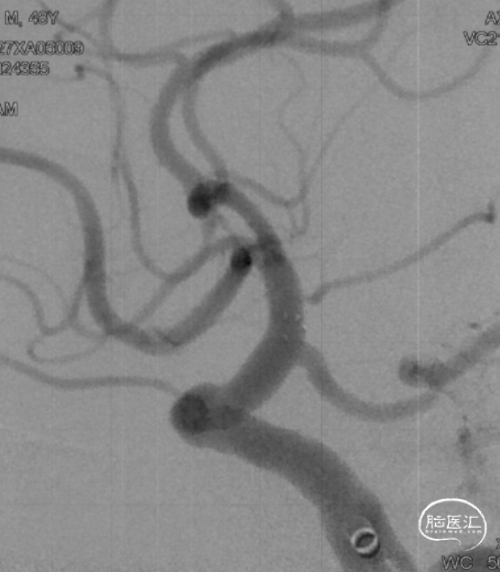

➤术前DSA检查

右侧大脑中动脉重度狭窄,左侧前循环未见明显异常。

病变部位: 右侧大脑中动脉M1段重度狭窄;狭窄率: 75.6%;狭窄长度: 6.10mm;参考远端血管直径: 1.27mm。

6F Envoy DA导引导管到位,Synchro2微导丝通过病变。

选用1.5-9mm 颅内球囊扩张导管通过病变。

10atm扩张90s。

泄球囊后可见狭窄明显改善。

选用赛诺神畅 3.5-20mm COMETIU™自膨式颅内药物涂层支架系统通过病变并缓慢释放,释放后造影,支架定位准确,完全覆盖病变,成形效果好。